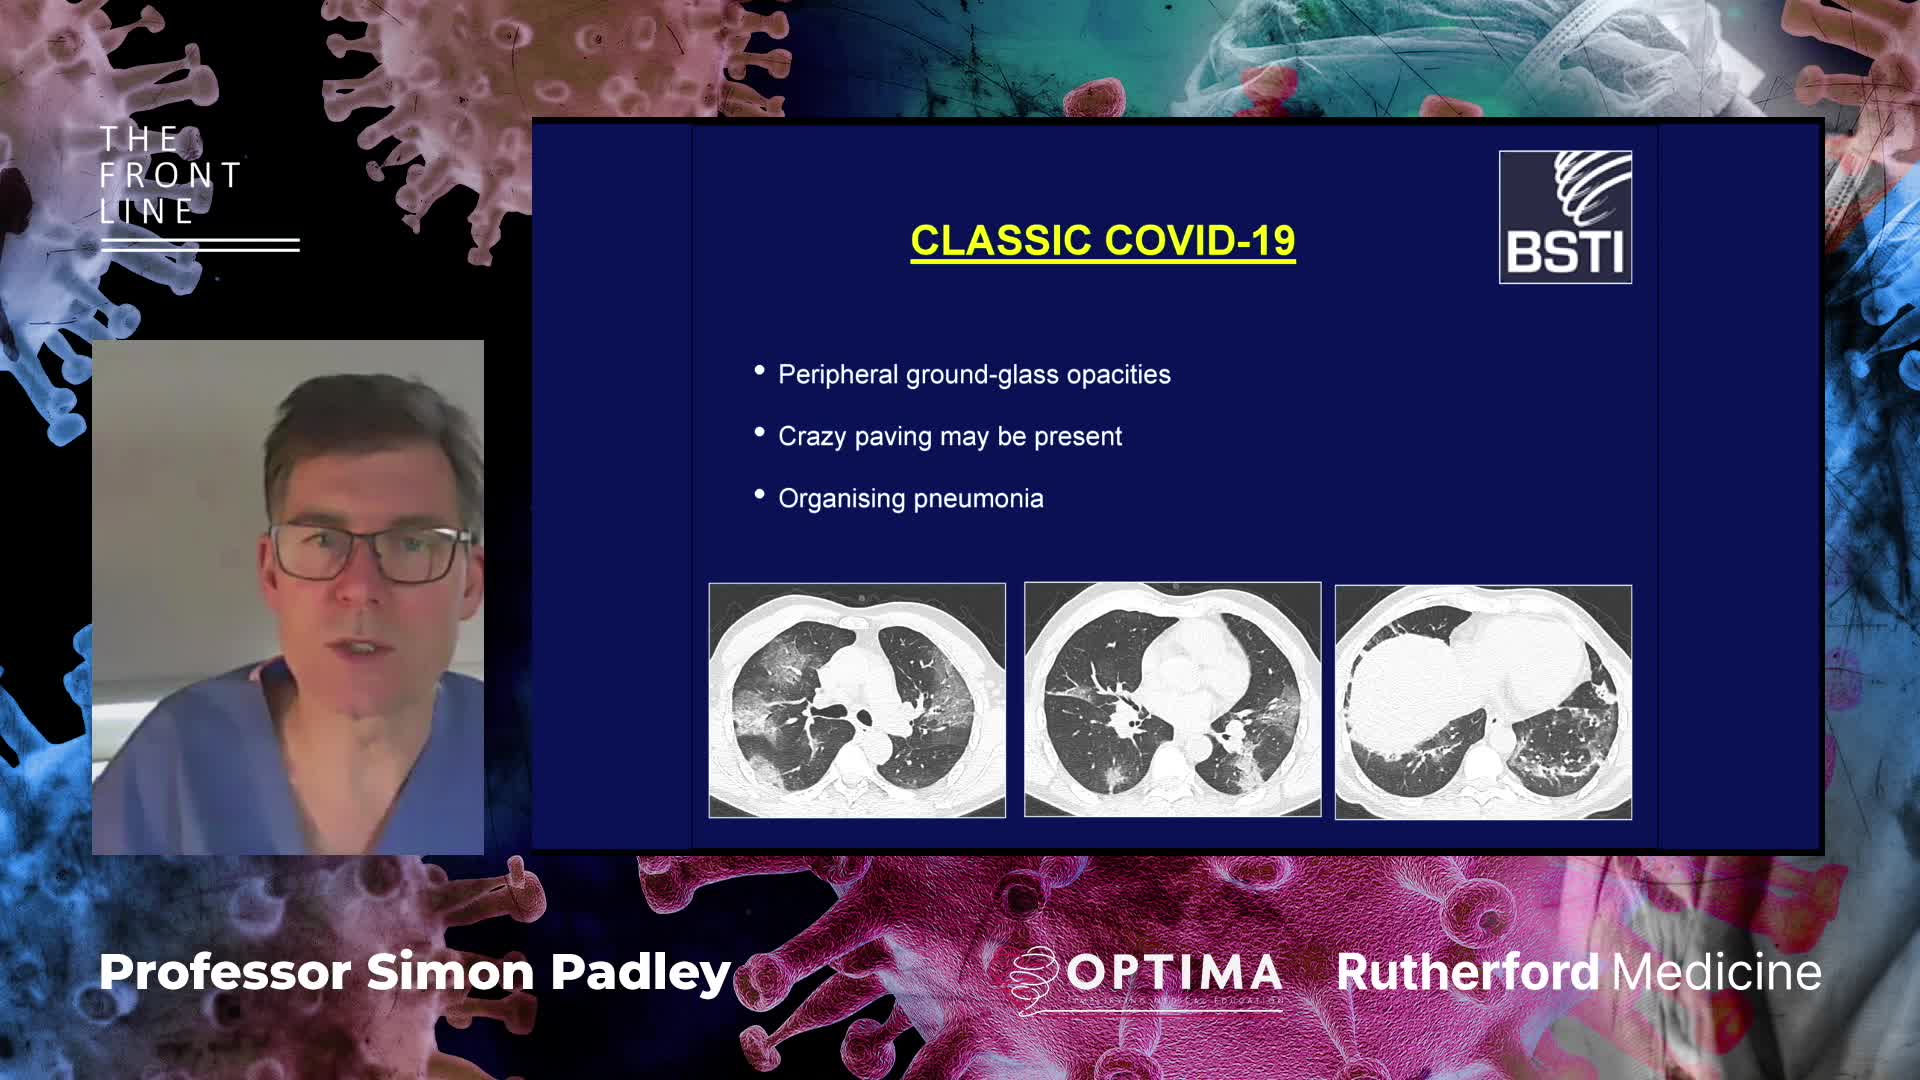

Past Courses: COVID-19

COVID-19: The Front Line. The Role of Extra Corporeal Membrane Oxygenation (ECMO) in the treatment of severe COVID-19